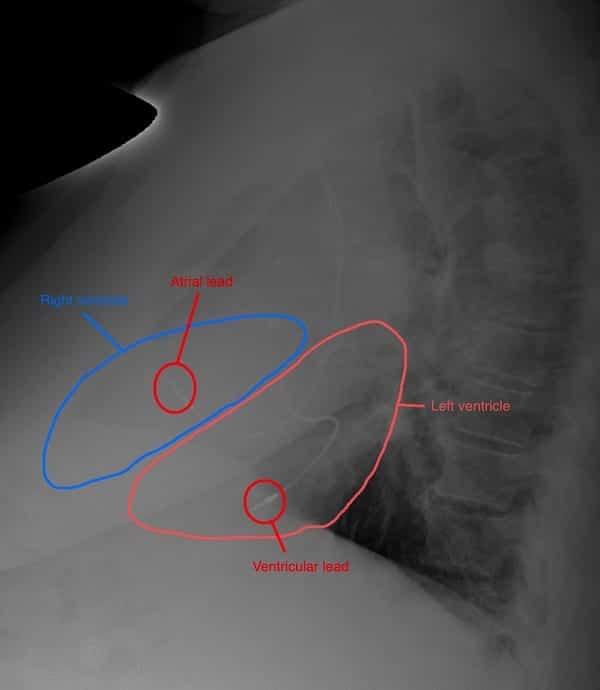

…so how about a lateral CXR?

For many of us the role of the lateral CXR is to localise or investigated pulmonary pathology, and we don’t always look at the cardiac silhouette. In this case an understanding of the lateral cardiac silhouette is essential to confirm our ECG suspected diagnosis.

Looking at this lateral CXR we can see one pacemaker lead sits anteriorly, and the other is sitting posteriorly, this is NOT normal.

On a lateral CXR the right ventricle sits anteriorly with the left ventricle sitting posteriorly.

This CXR confirms ventricular lead placement in the left ventricle.

The following PA and lateral CXR are taken from an unrelated case with appropriately placed pacing leads in the right atrium and right ventricle.

- Note the PA CXR appearance is not too different from the PA CXR in our case of lead misplacement

- Note on the lateral CXR both leads are placed anteriorly signifying right sided placement.

- Side-by-side comparison of cardiac silhouettes. Abnormal on left. Normal on right.